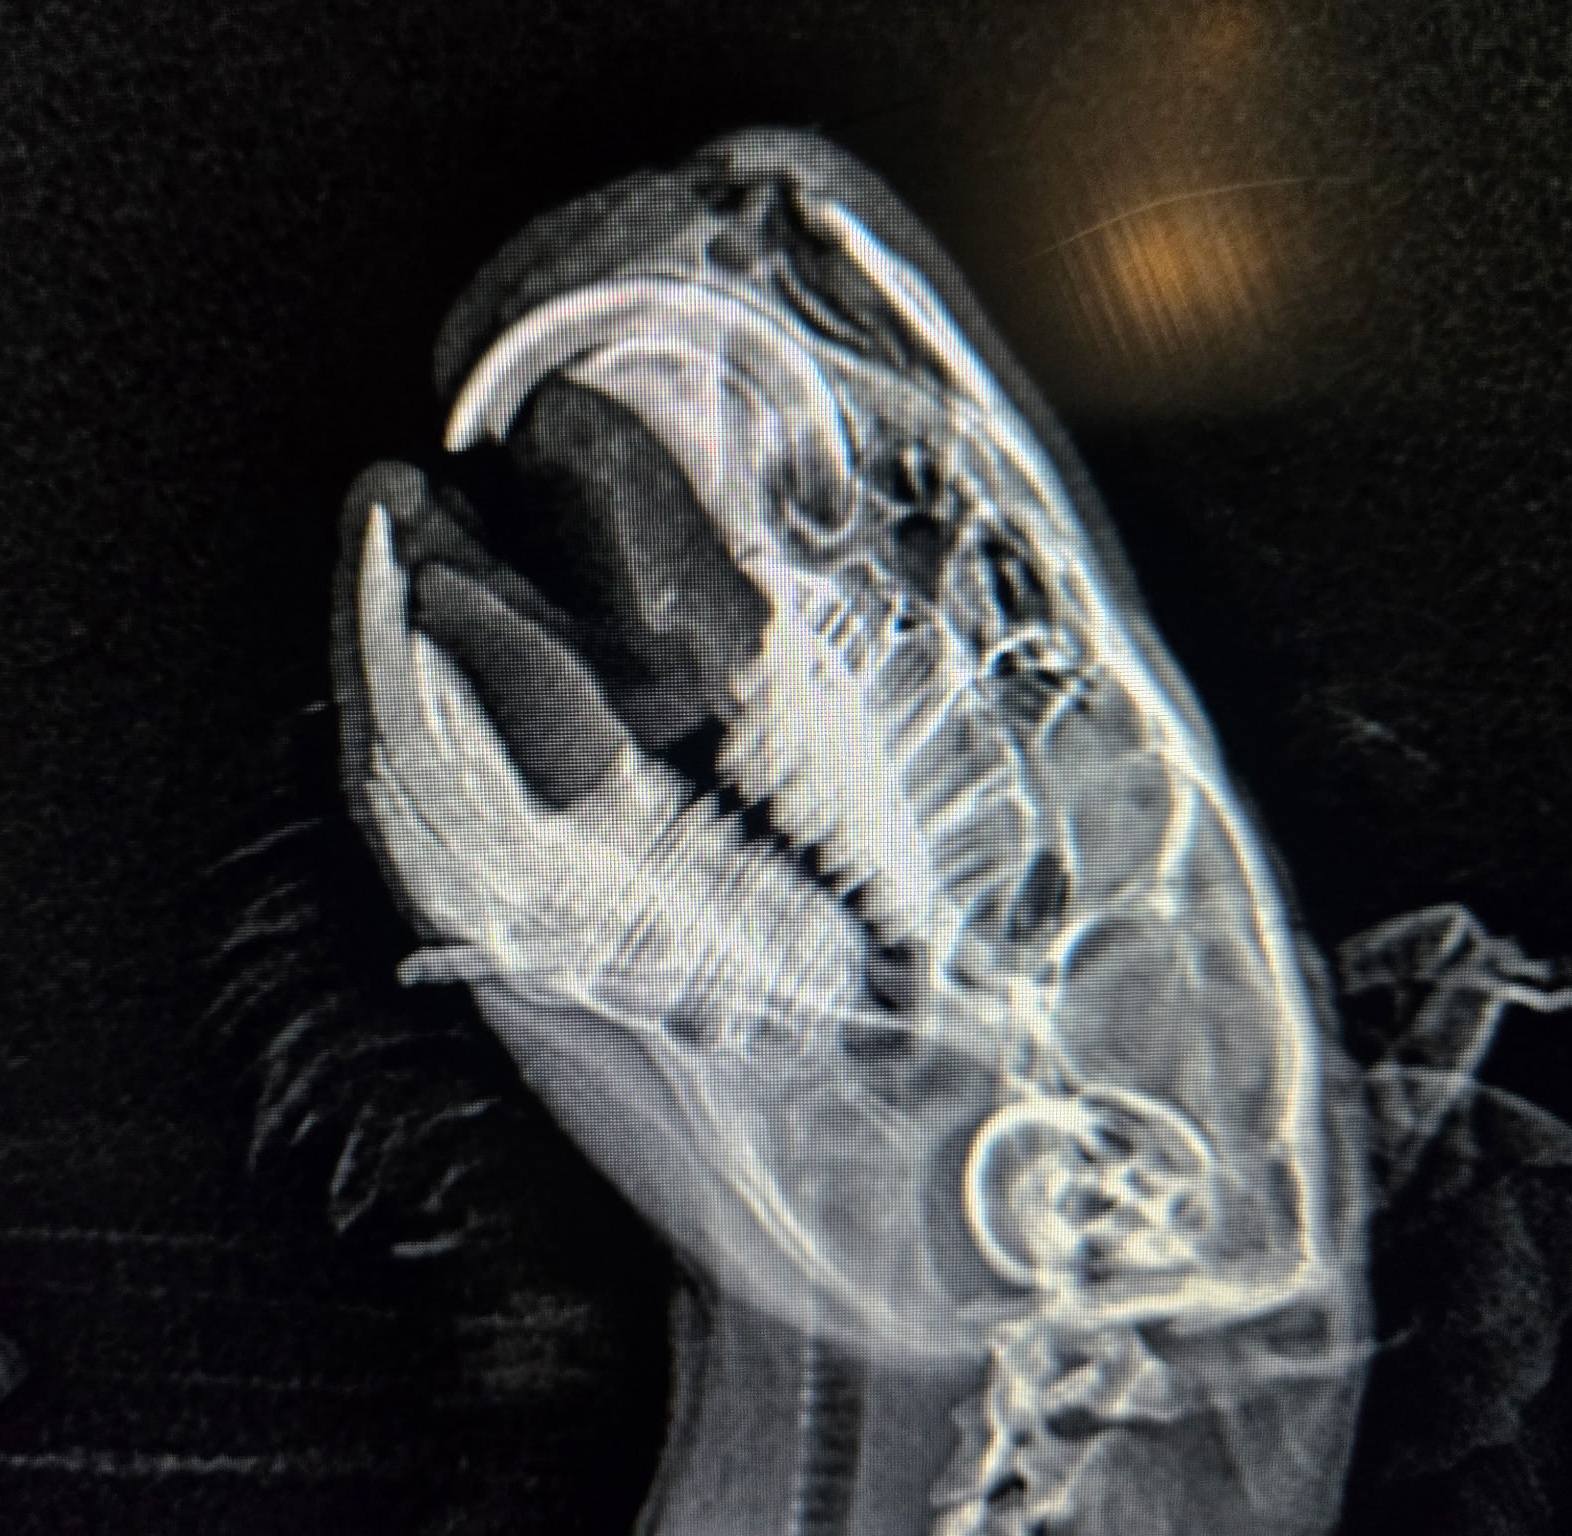

X-ray showing the broken incisor sideways through Toothless's jaw Dental radiograph showing the incisor fragment displaced sideways through the jaw.